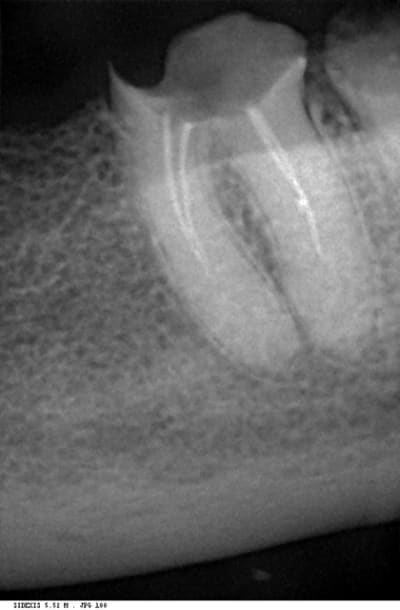

Est ce que cette molaire (36) est a extraire ou pas (ça m'est arrivé d'avoir une LIR a la suite d'une telle fragilisation du plancher )

Si elle est a traiter est ce qu'il faut une RTE même si la dent est asymptomatique (traitée depuis 5 ans)

les racines ont l'air solides,l'examen clinique du plancher devrait te guider dans ton choix,au pire faire une hemisection

moi je tenterai,si les canaux sont exposés,logiquement il faudrait les retraiter,faut voir avec ton patient et le prévenir que ce n'est pas gagné d'avance

Dans le cas présent, personnellement je pense qu'elle est conservable. C'est l'épaisseur résiduelle du plancher appréciable en clinique en complément de la radio qui permet de poser l'indication de conservation ou d'extraction.

Si elle doit etre conservée, bien entendu le retraitement endodontique est indispensable.

Maintenant, ici, avec un plancher aussi bas par rapport à l'os et aussi proche de la furcation, une fois les tissus cariés "excavés" et l'élongation coronaire réalisée, on sera devant une situation un peu (beaucoup) scabreuse, non ?